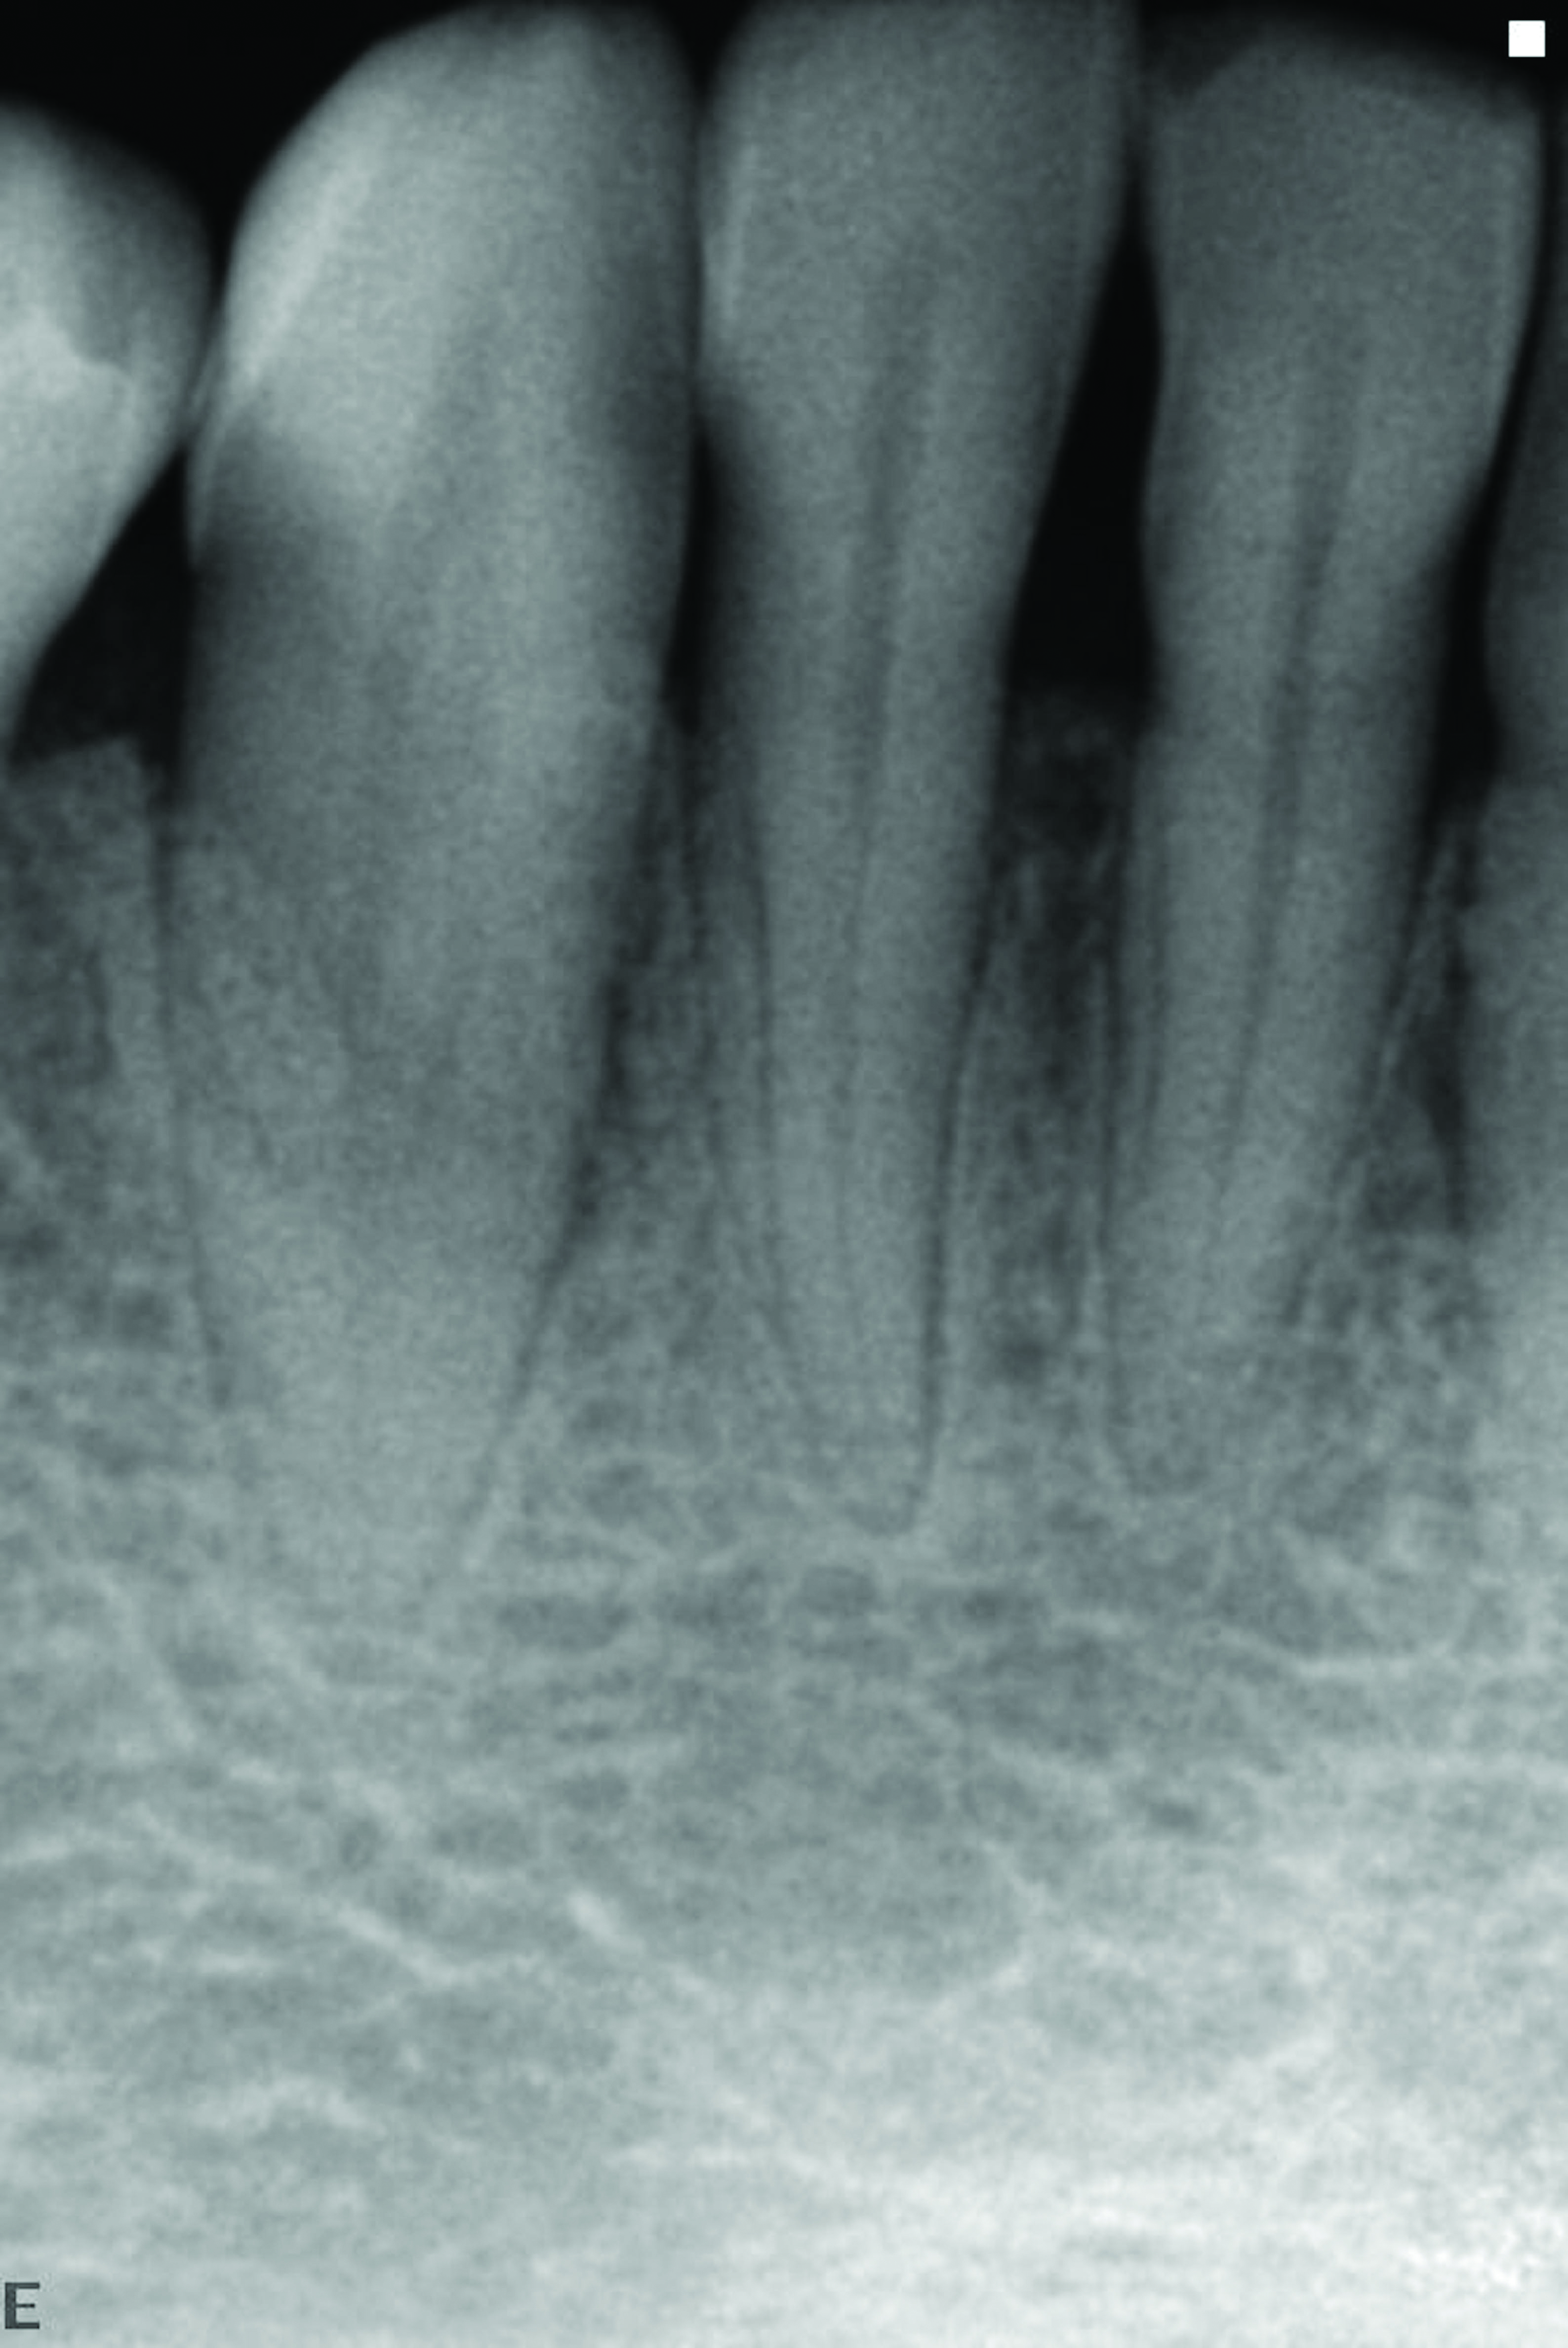

In a case with an intrabony defect, such as with the patient in Figure 17, a periodontist might suggest sacrificing supporting bone to remove the osseous defect. Doing this might lead to issues related to tooth mobility, esthetics, caries, and hypersensitivity.

The patient had been referred for an implant consultation for the mandibular right canine. She had very deep probing depths on the lingual. When the flap was raised, a significant amount of subgingival calculus was seen as a local risk factor (Figure 18). However, she had no significant pathology to remove from the situation. Debridement was performed the same as in Case 3 with the rotary ultrasonic and manual instrumentation.

A significant intrabony defect around tooth No. 27.

Figure 17

Subgingival calculus and severe bone loss.

Figure 18